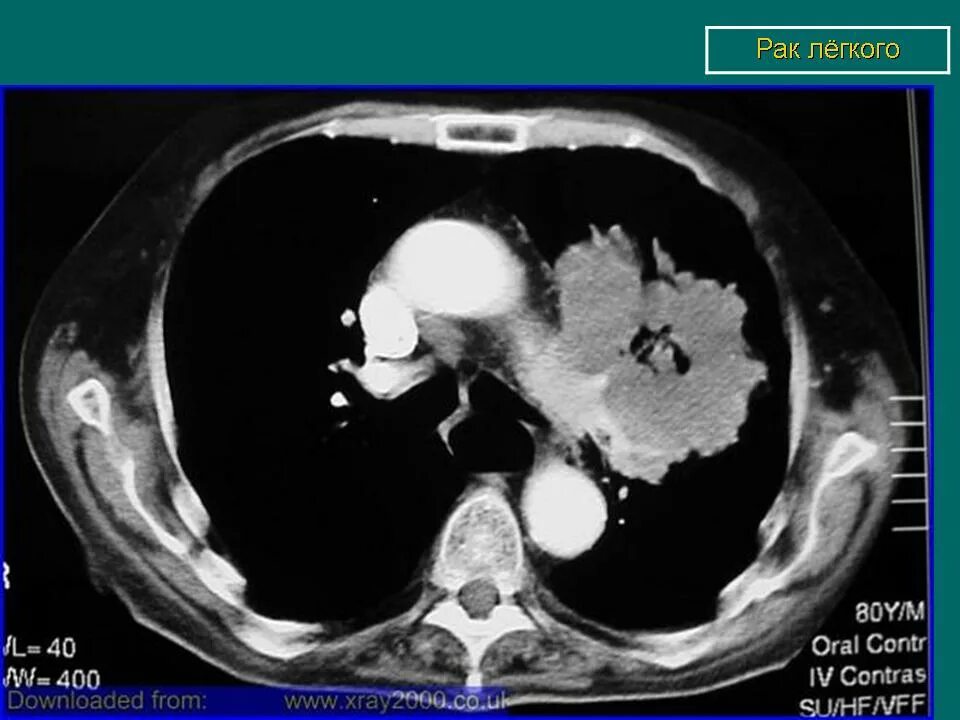

Лучевая при раке легких